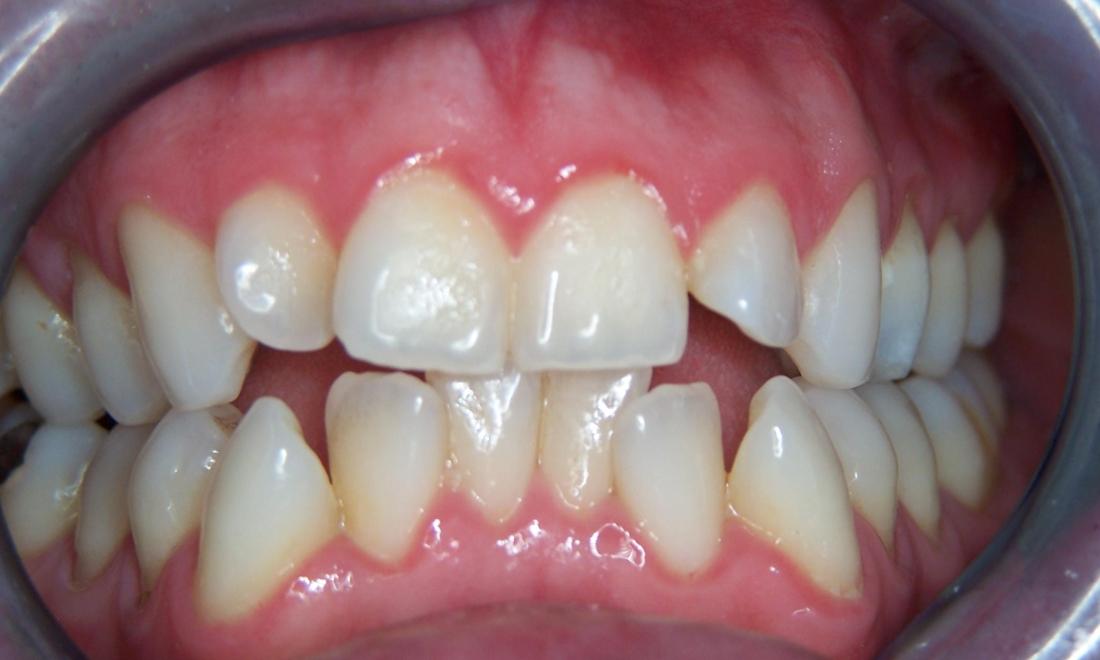

This patient's "before" photo shows their crooked, misaligned teeth and the gaps between the top and bottom rows of their smile. However, by using adult braces, we pulled their teeth into alignment and produced a straighter, healthier smile.